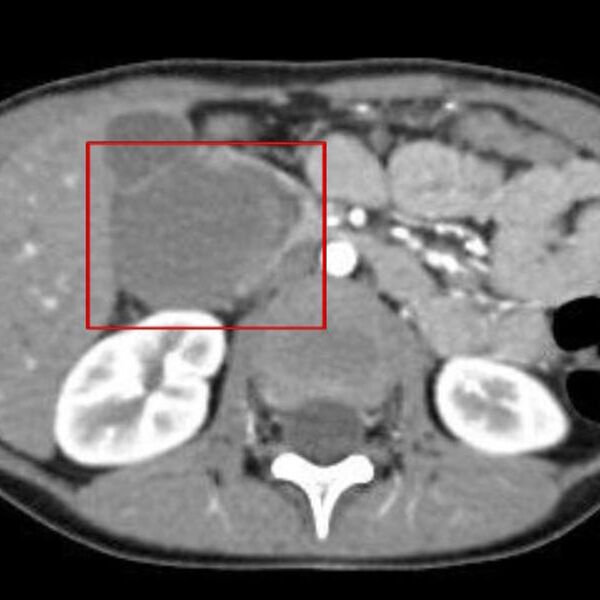

«Причиной кишечной непроходимости стала травма живота: после падения на подлокотник дивана у ребенка выросла гематома 52 мм на 48,5 мм», — пояснили в пресс-службе ведомства.

Пациенту провели лапароскопическую операцию. Во время нее хирурги обнаружили, что гематома образовалась между двумя слоями двенадцатиперстной кишки и, по их словам, «чудом ее не повредила». Специалисты добрались до гематомы и вскрыли ее.